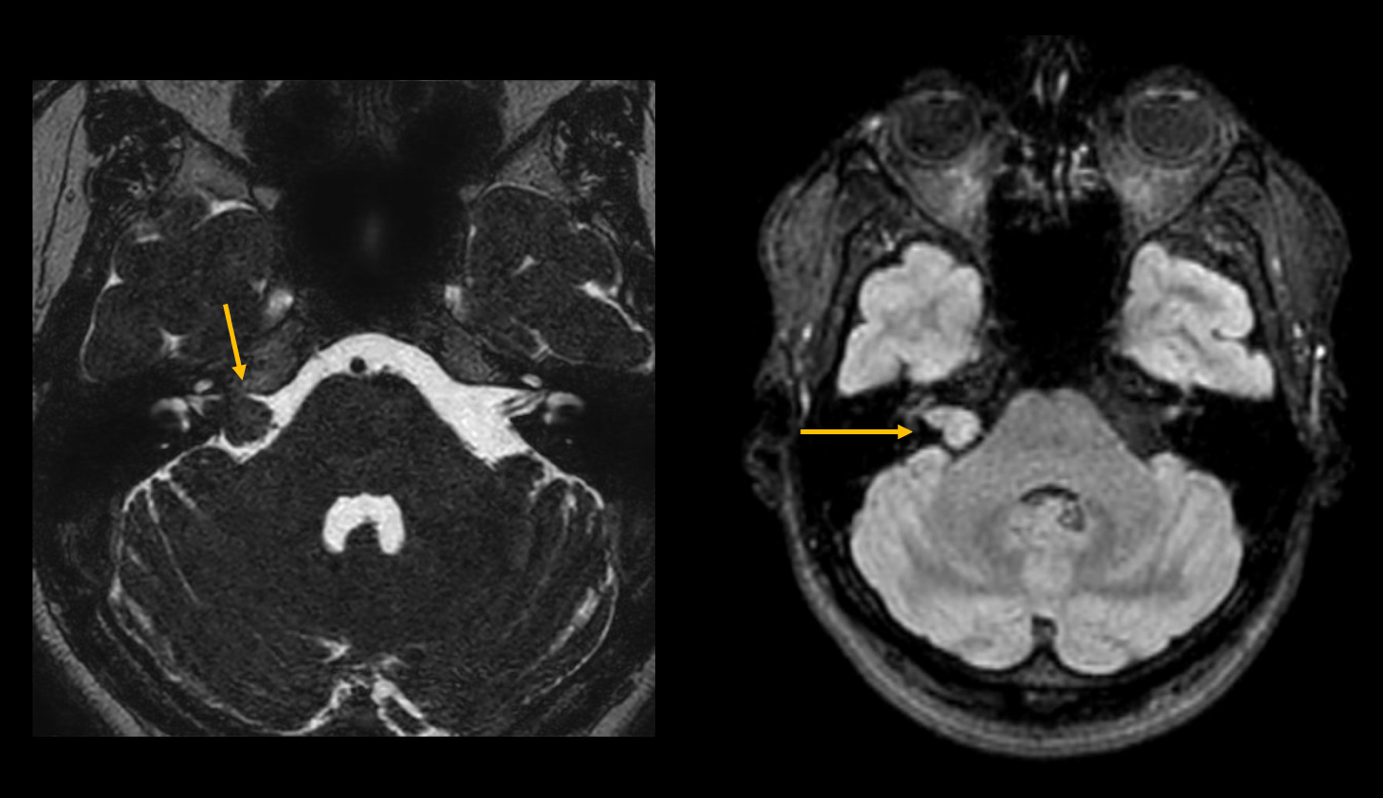

Bei einer 47-jährigen Patientin (siehe Abbildungen) wurde ein Akustikusneurinom auf der rechten Seite festgestellt, das zu einem Hörsturz führte.

Bild 2: MRT der hinteren Schädelgrube in T2- und T1-Wichtung. Hier zu sehen ist eine T2-W-isointense Raumforderung im meatus acusticus internus, vereinbar mit einem Akustikusneurinom.